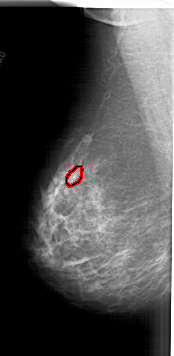

FILE: A_1905_1.LEFT_CC.OVERLAY

TOTAL_ABNORMALITIES 1

ABNORMALITY 1

LESION_TYPE CALCIFICATION TYPE PLEOMORPHIC DISTRIBUTION CLUSTERED

ASSESSMENT 4

SUBTLETY 3

PATHOLOGY MALIGNANT

TOTAL_OUTLINES 1

BOUNDARY